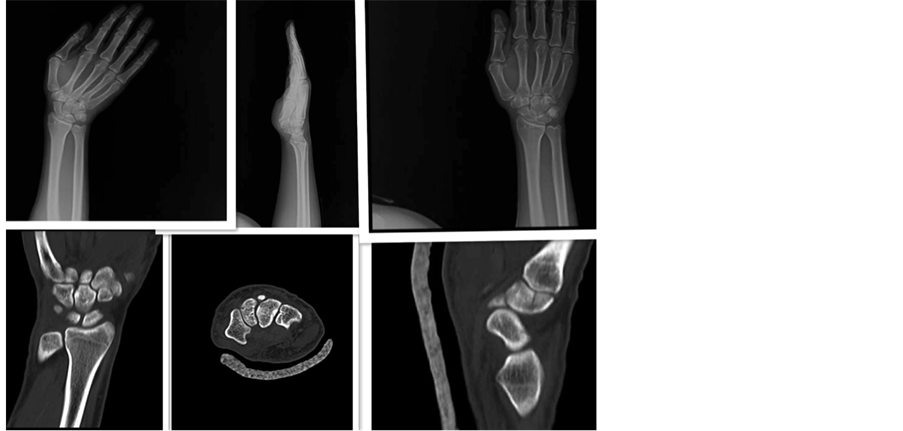

CT scan of the right and left wrists demonstrated a non-displaced trapezoid and non-displaced triquetrum fractures, respectively (Figure 1 and Figure 2).

Figure 1. Left hand AP; Left hand scaphoid view; Left hand lateral; Left hand axial CT (triquetrum fracture is observed); Left hand coronal CT; Left hand sagittal CT.

Figure 2. Right hand scaphoid view; Right hand lateral; Right hand AP; Right hand coronal CT; Right hand axial CT; Right hand sagittal CT (trapezoid fracture is observed).